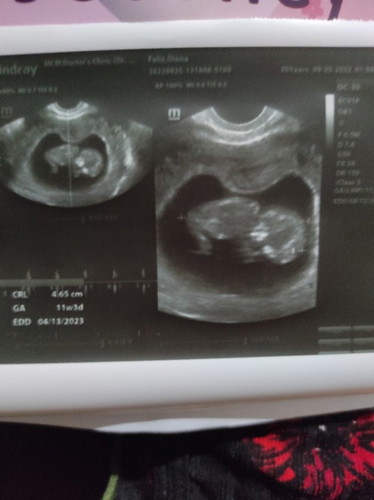

Okay lang po kaya na nakadapa si baby? At magbabago pa kaya posisyon nya? Salamat po.

11wks 3days first time mom

normal po yan sa ganyang mga gestational age. magbabago pa po yan